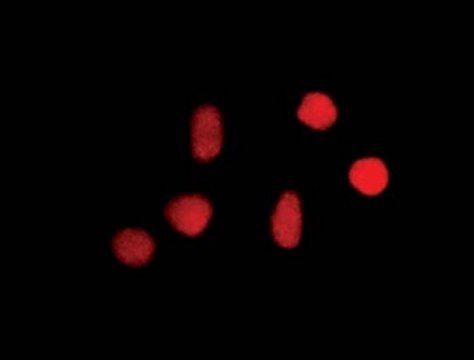

Immunocytochemistry:

Confocal fluorescent analysis of NIH/3T3 cells using anti-8-oxoguanine mouse monoclonal antibody.

On HeLa and Cos7 cells fixed with paraformaldehyde. 8-oxoguanine has been localized to the nucleus in nutrient-deprived cells.